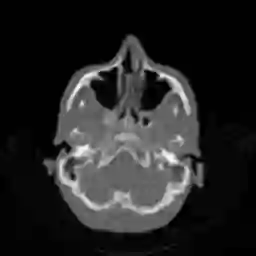

In this work, we propose Regularization-by-Equivariance (REV), a novel structure-adaptive regularization scheme for solving imaging inverse problems under incomplete measurements. Our regularization scheme utilizes the equivariant structure in the physics of the measurements -- which is prevalent in many inverse problems such as tomographic image reconstruction -- to mitigate the ill-poseness of the inverse problem. Our proposed scheme can be applied in a plug-and-play manner alongside with any classic first-order optimization algorithm such as the accelerated gradient descent/FISTA for simplicity and fast convergence. Our numerical experiments in sparse-view X-ray CT image reconstruction tasks demonstrate the effectiveness of our approach.